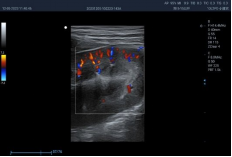

6C1PDA ● 2.5-13.5MHz ● Micro convex array probe ● For Abdomen, Cardiology, Reproduction |

![]() |